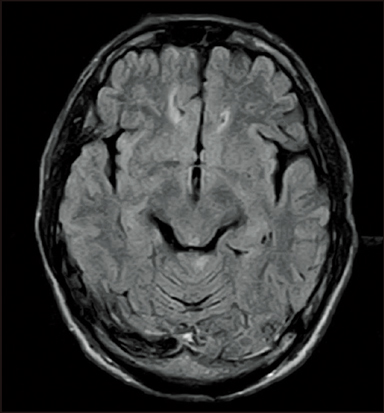

FLAIR